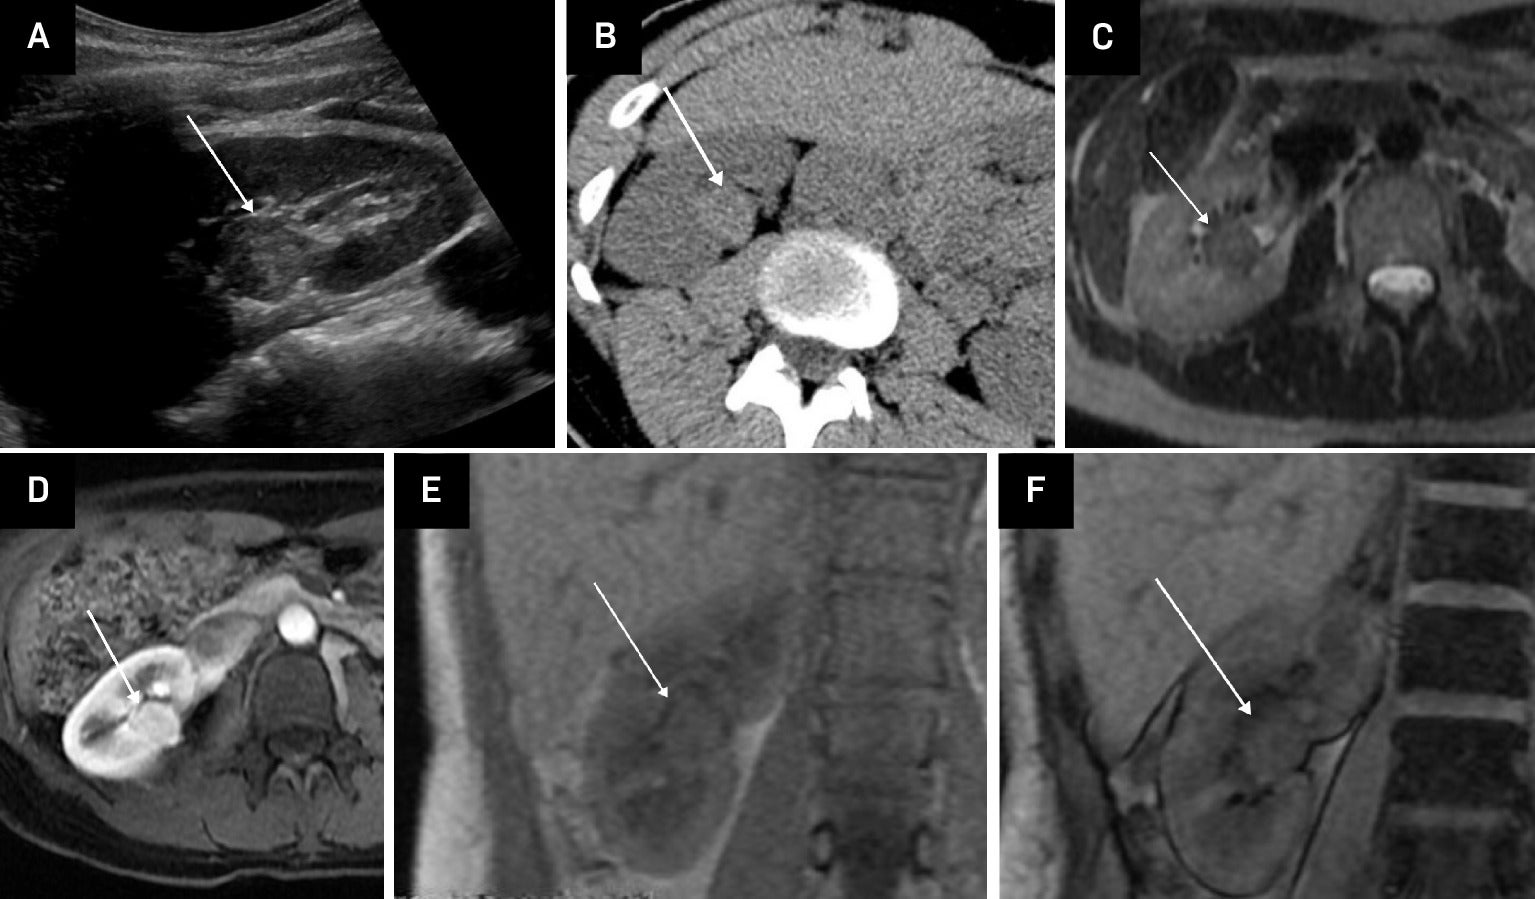

On MRI, a hyperattenuating AML appears hypointense on T2-weighted images ( Figure 2 , Table 1 ), whereas ccRCCs are typically hyperintense, aiding their differentiation. However, papillary RCC (pRCC) can also appear hypointense on T2, potentially mimicking fpAML. As with density comparisons on CT, the T2 signal intensity (SI) of these masses on MRI can be quantified using the TCR, which compares the SI of the mass to that of the spleen or adjacent renal cortex. In a study by Jeong et al, the mean TCR for fpAML was 0.75, significantly lower than the 1.21 reported for ccRCC.5 Setting the TCR threshold at 0.86 achieved a sensitivity of 93% and a specificity of 82% for distinguishing fpAML from ccRCC.

Hyperattenuating fat-poor angiomyolipoma (fpAML) in an adult female. US of the right kidney showing an echogenic mass (arrow) (A). Non-contrast CT shows the mass to be hyperattenuating, with Hounsfield units >45 (arrow) (B). Axial single-shot fast spin echo (SSFSE) T2-weighted MRI shows the mass to be of low signal intensity (arrow) (C). Contrast-enhanced LAVA FLEX (FAT SAT) MRI shows early contrast enhancement of the mass (arrow) (D). Chemical shift imaging with in-phase LAVA FLEX coronal MRI showing the mass (arrow) (E). Chemical shift imaging with out-of-phase LAVA FLEX coronal MRI shows no signal drop-out within the mass (arrow) indicative of no microscopic fat (F).

Chemical shift imaging may assist in distinguishing fpAMLs from pRCCs.5 Most fpAMLs demonstrate no signal loss on out-of-phase chemical shift images, although occasional small foci of signal drop may be present due to microscopic fat ( Figure 2 ). By comparison, ccRCCs possibly show diffuse signal loss on opposed-phase imaging due to the presence of intracytoplasmic lipid.3, 4

On contrast-enhanced imaging, fpAMLs are usually homogeneously avidly and rapidly enhancing, whereas pRCCs demonstrate delayed contrast enhancement.7 Arterial-to-delayed enhancement ratios on MRI have been proposed to differentiate fpAMLs from RCC subtypes. Using dynamic contrast-enhanced spoiled gradient-echo images, arterial, venous, and 3-minute-delayed phases can be obtained. A 5 mm or larger region of interest is placed in the most arterial enhancing portion of the mass as the SI. The ratio is calculated as follows: (ST arterial – SI pre)/(SI delayed – SI pre). An arterial-to-delayed enhancement ratio >1.5 for T2-hypointense lesions can aid differentiation between the fpAMLs and all subtypes of AMLs.8